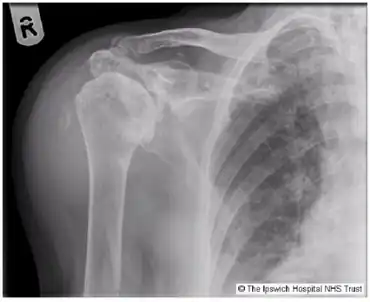

Milwaukee shoulder syndrome X-ray.

Milwaukee shoulder syndrome (MSS) (apatite-associated destructive arthritis/Basic calcium phosphate (BCP) crystal arthritis/rapid destructive arthritis of the shoulder[1] is a rare[2] rheumatological condition similar to pseudogout, associated with periarticular or intra-articular deposition of hydroxyapatite or basic calcium phosphate (BCP) crystals. While primarily associated with the shoulder joint, it can affect any joint in the body below the head.[3] Along with symptomatology, the disease typically presents with positive radiologic findings, often showing marked erosion of the humeral head, cartilage, capsule, and bursae. Though rare, it is most often seen in females beginning in their 50s or 60s. Patients often have a history of joint trauma or overuse, calcium pyrophosphate dehydrate crystal deposition, neuroarthropathy, dialysis-related arthropathy or denervation.[2]

Diagnosis is made with arthrocentesis and Alizarin Red staining along with clinical symptoms.[6] X-rays, arthrography, ultrasonography, CT imaging and MRI imaging are also helpful in diagnosing this condition